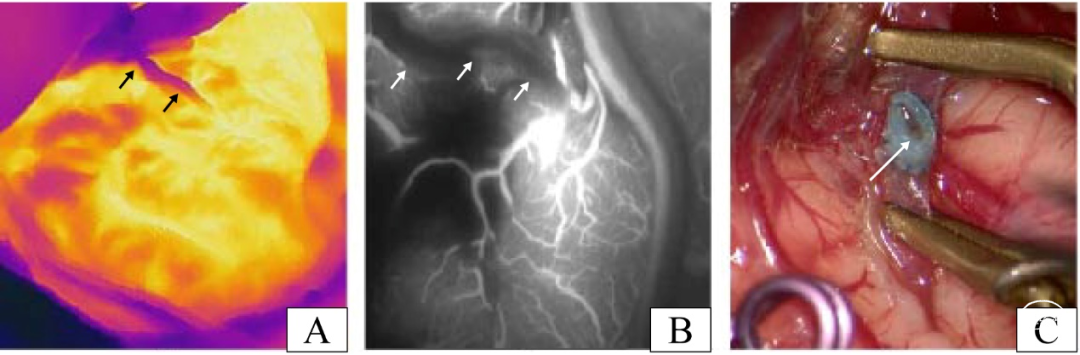

其中一名患者术中应用红外热成像评估后怀疑吻合口通畅性不足,而吻合口的ICG-VA评估结果证实确实存在吻合口梗阻(图4A,B)。打开颞浅动脉观察吻合口内部情况后,从图4C可以看到血栓,我们考虑该血栓形成是本例吻合口梗阻的原因。这进一步证明了红外热成像和ICG-VA在评估吻合口通畅性方面的一致结果。随后,该病例通过拆除吻合口并清除血栓后重新进行了吻合。

图4. 一位血管吻合口不通畅的患者。(A)该患者释放血管夹后的红外热成像结果(黑色箭头表示STA)。(B)该患者释放血管夹后的ICG-VA图像结果(白色箭头表示STA)。(C)在剪开颞浅动脉后发现血栓,是导致该病例血管吻合口不通畅的原因(白色箭头表示吻合口的血栓)。